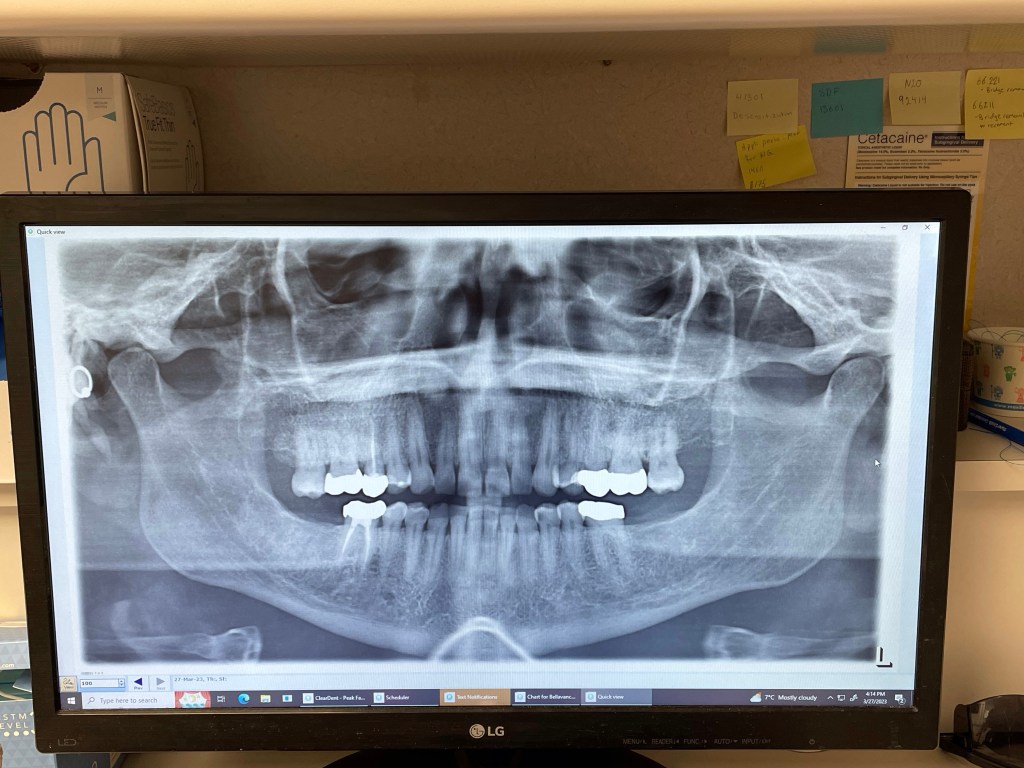

I was in the dentist chair this afternoon when Rae-Anne called and it rang through due to my settings. Those in the office around me had a good laugh. I found the machine that did a full panoramic X-ray quite fascinating and I am told everything is in good shape considering how long I have had these teeth. The crowns and root canals show up well.